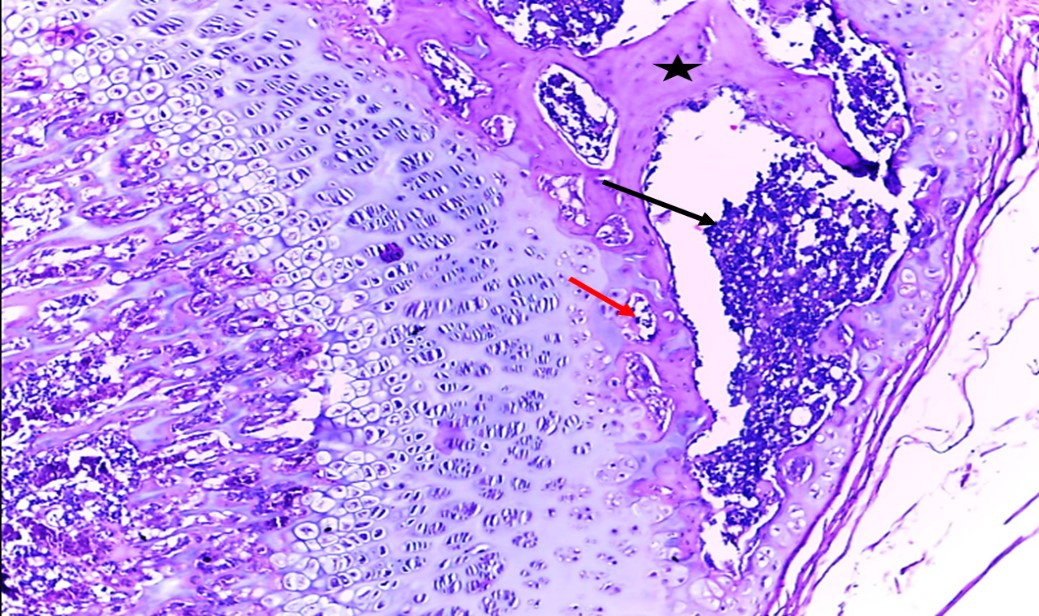

as shown Histologic al alterations in femur bone in rats with zinc deficiency in (Fig 2), involved loss of trabecular mass especially compact bone and altered osteoclast activity in the bone tissue were evaluated by atrophy in osteoblast and then decrease in bone density as compared to femur bone in rats without zinc deficiency in (Fig1) which characterized by normal architecture bone tissue showing normal compact (black star), spongy bone(black arrow) normal osteoblast (red arrow), osteoclast(yellow arrow) and normal trabecular (green arrow). Whereas the administration of zinc and Vit D cause to restoration these histological changes which including significantly improve in the trabecular mass (compact and spongy bones), improve bone density as well improve tissue remodeling and semi normal trabecular mass with normally distribution of osteoblast and osteoclast (red arrow) with good appearance of compact and spongy bone as shown in (Figs 3 and 4), the above changes in femur bone as comparison to femur bone in (Fig 2).

Figure (1).